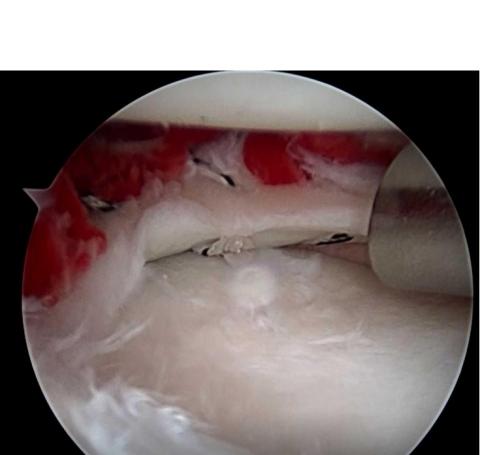

Un suivi post-opératoire de 30 cas de chirurgie méniscale associée à un caillot de fibrine BMA (voir visuel ci-contre) confirme des améliorations significatives de l'état du ménisque par rapport aux résultats préopératoires. Les évaluations radiographiques ne montrent aucune progression significative de la déformation du genou.